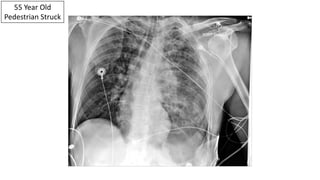

55 Year Old

Pedestrian Struck